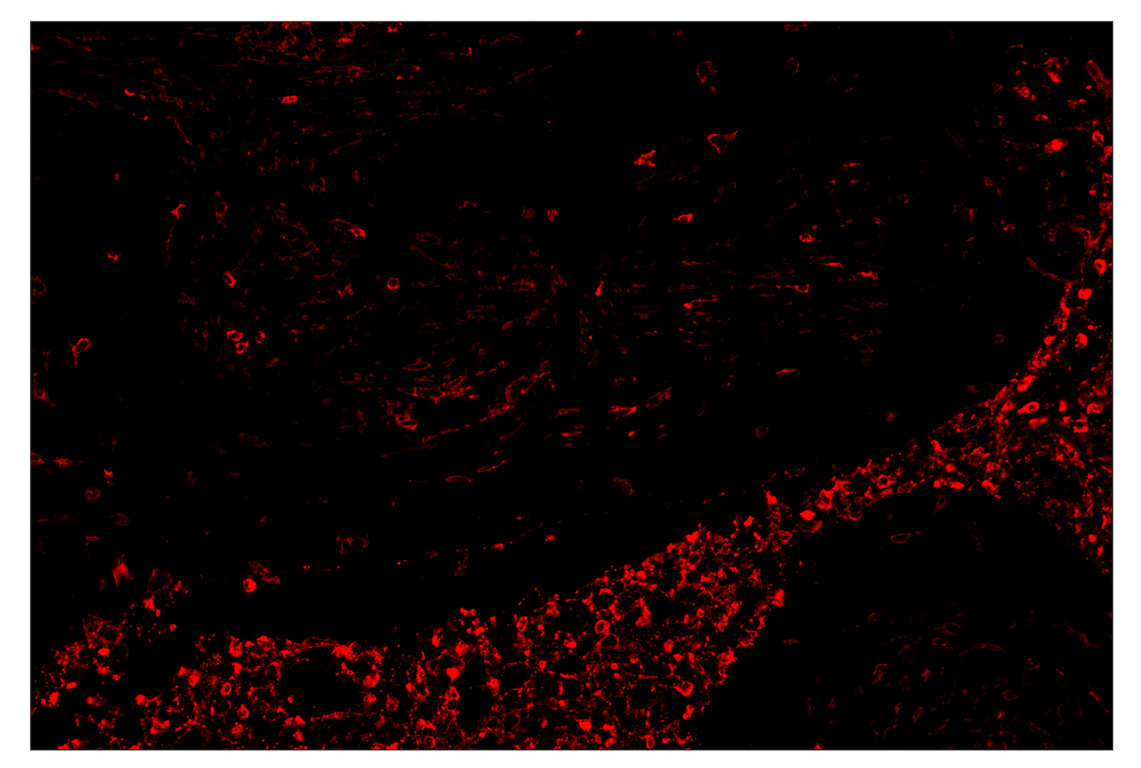

SignalStar™ immunohistochemical analysis of paraffin-embedded human squamous cell lung carcinoma using CD11b/ITGAM (D6X1N) & CO-0037-647 SignalStar™ Oligo-Antibody Pair #29052 (red). All fluorophores have been assigned a pseudocolor, as indicated. Staining was performed on the BOND RX autostainer by Leica Biosystems.

Immunohistochemistry Image 4: CD11b/ITGAM (D6X1N) & CO-0037-647 SignalStar<sup>™</sup> Oligo-Antibody Pair